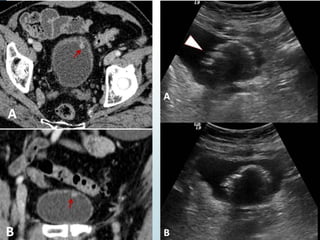

• #15 DISPLASIA UROTELIAL. Imágenes axiales de TCMD realizado en fase nefrográfica (A) y en fase excretora (B) que muestran la presencia de dos pequeñas proliferaciones papilares en la pared antero-superior de la vejiga urinaria (flechas y punta de flecha).

• #16 DISPLASIA UROTELIAL. A) Imagen axial e imagen coronal (B) por TC que muestran las pequeñas proliferaciones papilares. CARCINOMA UROTELIAL papilar con FENOTIPO PLASMOCITOIDE. La ecografía (A,B) muestra una ocupación de la luz vesical por una tumoración sólida de aspecto sésil.